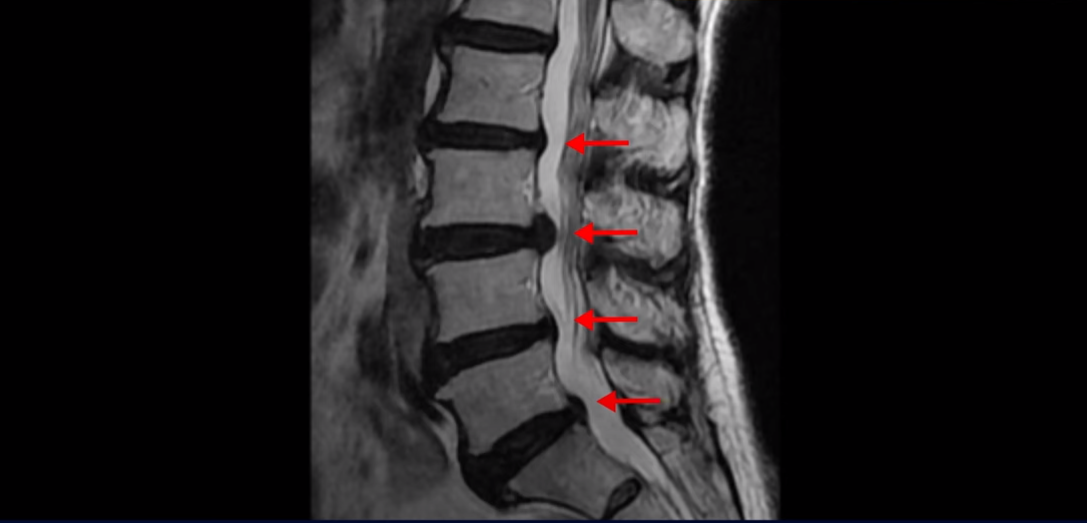

먼저 이분 MRI 보면서 간단히 설명 드린 후 어떻게 신경이 눌려서 수술해야 된다는 환자를 수술 없이 치료할 수 있는지 또 치료는 어떻게 하는지 자세히 설명 드리겠습니다. 이분 허리 MRI를 보면 여러 마디가 퇴행되어 있고

3번 4번 마디에 디스크 파열이 있습니다.

하지만 이 디스크 파열은 오래된 걸로 보이며, 지금 이 환자분의 아픈 양쪽 다리 특히 양쪽 발의 통증, 발 시린 증상과는 관련이 없어 보입니다. 오른쪽 왼쪽의 신경가지가 빠져나가는 추간공을 보면 오른쪽은 5번 1번과 4번 5번이 많이 좁아져 있고

왼쪽은 5번 1번이 많이 좁아져 있습니다.

이렇게 오른쪽 왼쪽 양쪽 추간공들이 다 좁아져 있고 신경가지들이 눌려있으니까 양쪽다리와 양쪽 발이 저리고 시리고 아파서 걷기 어렵습니다. 그런데 이 환자분은 신경주사를 여러 번 맞아도 듣지를 않는데요. 이렇게 신경주사가 듣지 않으면 십중팔구 수술밖에 방법이 없다는 얘기를 듣습니다. 그럼 어떻게 이런 신경이 눌려있는 환자분들을 수술 없이 치료해서 잘 걷게 만들고 다리와 발이 저리고 시리고 아픈 증상이 사라지게 만들까요? 지금부터 설명해드립니다.